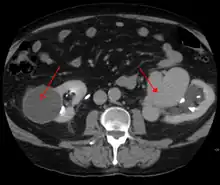

An arterial venous malformation of the left kidney leading to aneurysmal dilatation of the left renal vein and inferior vena cava